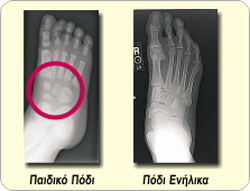

Η σωστή μέτρηση του ποδιού είναι ιδιαίτερα σημαντική στο παιδικό πόδι για τους εξής λόγους:

Το παιδικό πόδι δεν διαθέτει ακόμα τα 26 οστά όπως το πόδι ενός ενήλικα αλλά περιέχει εύπλαστους χόνδρους οι οποίοι χρειάζονται πολλά χρόνια μέχρι να μετατραπούν σε οστό.

Η οστεοποίηση στο παιδικό πόδι δεν ολοκληρώνεται πριν την ηλικία των 18-20 ετών και μέχρι τότε, τα οστά και οι αρθρώσεις παραμορφώνονται εύκολα όταν υποβάλλονται σε υπερβολική πίεση από τα στενά παιδικά παπούτσια! Τι νούμερο παπούτσι φοράω